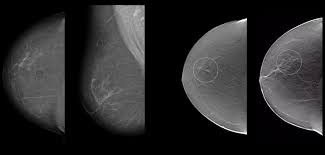

Mamografía digital en CDMX

Mamografía digital

Estudio esencial para detección oportuna y valoración mamaria con imágenes de alta calidad.

Mastografía 3D o tomosíntesis

Mastografía 3D / Tomosíntesis

Valoración más detallada del tejido mamario para complementar la revisión clínica y por imagen.

Muchas lesiones mamarias no presentan síntomas en etapas iniciales. Por eso, estudios de imagen como la mastografía, el ultrasonido de mama y la resonancia mamaria son fundamentales para detectar cambios de forma oportuna, valorar con mayor precisión el tejido mamario y decidir el seguimiento más adecuado en cada caso.